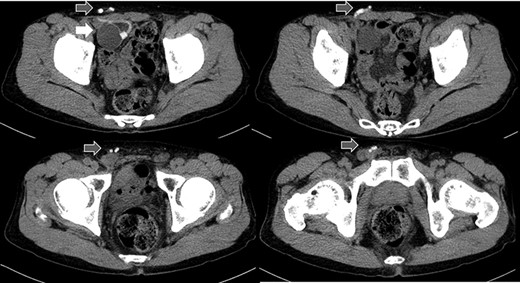

A 75-year-old male was referred for the treatment of a right IH. He also had received AUS implantation for a similar medical course. Abdominal CT demonstrated that a balloon was located beside the bladder and that the connecting catheter went through the rectus abdominis muscle and reached to the right scrotum through the subcutaneous layer (Fig. 5). The catheter was palpable subcutaneously; therefore, skin incision was placed on the outer site rather than in the normal situation. The diagnosis was indirect hernia and we did not observe any components of the AUS in the inguinal canal and repaired it using the Lichtenstein method.

Abdominal CT in Case 2: the balloon was located near the bladder and the tube went through rectus abdominis muscle; balloon, white arrow; tubes, gray arrows.

There is a report that contraindicates the laparoscopic repair for IH because of scaring and adhesion after RP in the preperitoneal space [4]. In addition, it is difficult to avoid damage to the AUS device without tactile perception. Therefore, we chose an anterior approach, which is the most familiar method for us. The operation of Case 1 patient was difficult because of adhesion in the inguinal canal, but Case 2 was not. The difference between the two cases was whether the catheter went through inguinal canal or not. We could detect the tract of the catheter by preoperative CT and US, which could be a good predictor for adhesion or difficulty in the operation.